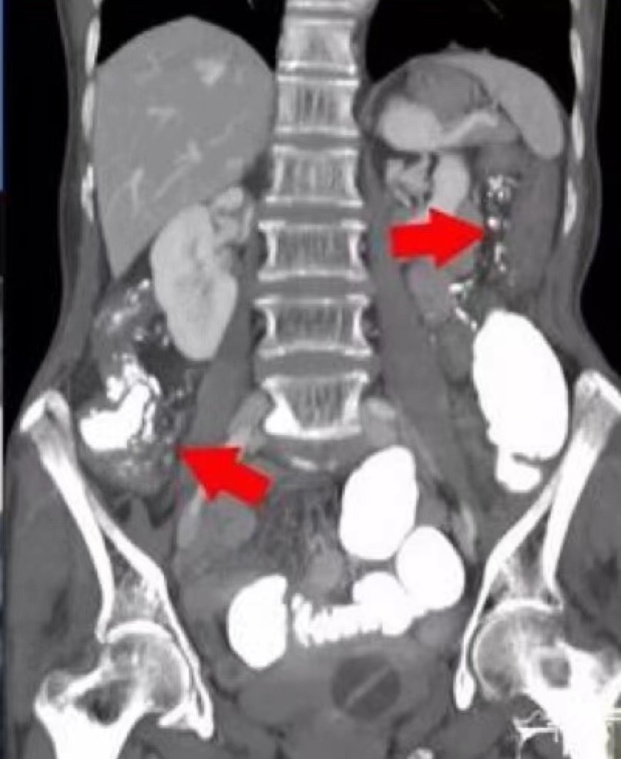

保守治疗并没有起到明显效果。CT检查显示,老蒋的回盲部已经出现了包裹性积液。老蒋的结肠肠壁明显增厚,肠系膜静脉里充满了砂砾状的钙化灶,这导致结肠静脉回流受阻。

为此,余医生决定马上为老蒋进行开腹探查,余医生发现整个肠壁充血、水肿扩张得厉害,已经导致大部分结肠缺血坏死,并发生了慢性穿孔,判断老蒋可能患上了“特发性肠系膜静脉硬化性结肠炎”。